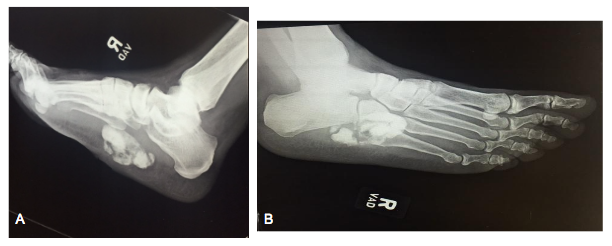

Figure 1 Preoperative medial oblique (A) and lateral (B) radiographic views demonstrating a radiopaque mass of the plantar midfoot with no bony involvement.

This is the case of a 70 year old male who was treated by us from 9/2015 to 2/2016. The patient, who had no known allergies, had a past medical history of Insulin Dependent Diabetes Mellitus, prostate cancer, and renal cell carcinoma, was referred to our service by an orthopedic colleague. The patient complained that he began noticing a swelling 6 months prior on the plantar medial arch of his right foot. As per the patient, the mass continued to increase in size leading to pain for which the biopsy was taken on 9/9/2015, confirming the diagnosis of chondroma. Since then, the patient had pain upon initial standing and some discomfort while walking. Approximately 2-3 days prior to admission, the patient noticed swelling and redness to the plantar surface. On the day of admission, patient presented with right foot cellulitis, chills, and a temperature of 103 F. Upon examination, a firm, non-mobile swelling was present in the plantar arch of the right foot with a central area of ulceration measuring roughly 3 cm in diameter. On palpation, the swollen area was found to be excessively warm and tender. The ulcer was superficial with well-defined margins and no veins were dilated. No distal neurovascular deficit or defined proximal lymphadenopathy was present. The blood investigations revealed a hemoglobin of 13.8 g/dl, leukocytosis with a white blood cell count of 14,900, and erythrocyte sedimentation rate of 3 mm at 1 hour. Culture of the wound was positive for methicillin sensitive Staphylococcus aureus. Plain radiographs of the foot, both lateral and oblique views, revealed a radiodense extraskeletal mass in the plantar arch that did not seem to distort the normal osseous anatomy of the right foot (Figure 1). Computed Tomography imaging was performed to evaluate the size and extent of the lesion, which was found to be contiguous with the plantar fascia. The approximate size was estimated to be 2.9x6.2x4.0 cm (71.92cm³). Surgical removal of the mass was planned after the resolution of infection. Infectious Disease was consulted and the patient was treated with intravenous Ceftriaxone 1gm daily (following the initial single doses of intravenous Vancomycin 1 gm and Zosyn 4.5 gm upon admission) and was evaluated daily for the control of infection. Once the patient was optimized for surgery, we began our procedure as follows: the patient was positioned in the supine position under general anesthesia. The foot was exsanguinated and an ankle tourniquet was inflated to 250 mm/Hg. The plantar wound was found to measure roughly 3 cm in diameter. Incisions were made taking 0.5 cm margins on both the medial and lateral sides equally. A fusiform excision technique was used which resulted in the creation of a wound that was 4 cm wide and 12 cm long. Using meticulous blunt and sharp dissection, the redundant wedge of skin was excised, including the wound itself. A large chondral mass was subsequently encountered, which was contiguous with the deep and plantar fascia and approximately 9x4x3 cm (108 cm³) in dimension (Figure 2). As it was in close proximity to the deep neurovascular structures, a small sensory branch of lateral plantar nerve was sacrificed. After thorough excision of the mass, the surgical site was copiously irrigated with 50,000 units of a Bacitracin and Polymyxin solution. The deep plantar fascia was repaired using 2-0 Vicryl suture. The wound was then approximated using the DermaClose® tissue expander to decrease the tension on the surrounding skin and subcutaneous tissue. Given the large size of the defect, soft tissue edema, and patient’s history of diabetes, it was deemed necessary to utilize the device. Application began with the placement of three anchors on the medial and distal sides of the incision. The anchors were applied roughly 1 cm from the wound margins and 1.5 cm from each adjacent anchor, and were subsequently secured with skin staples. The appropriate, associated lacing technique of the corresponding tension line was then employed. Tension was applied by turning the knob on the device to the desired position, thus pulling the line through a tube system, which was placed across the medial arch.